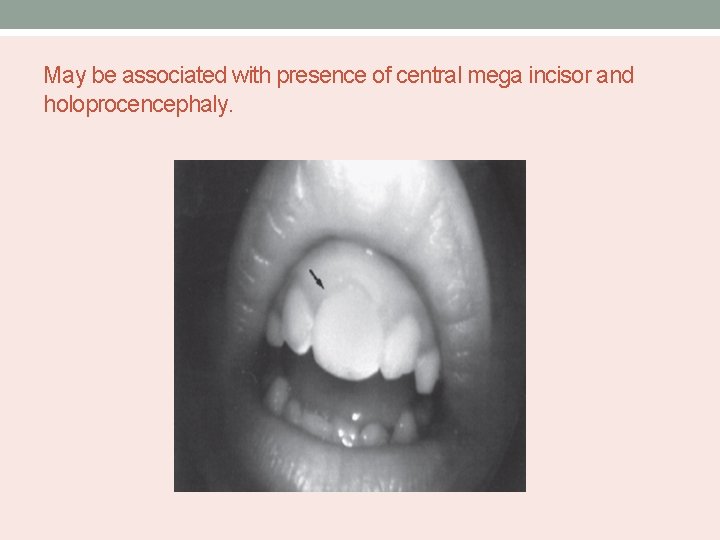

May be associated with presence of central mega incisor and holoprocencephaly.